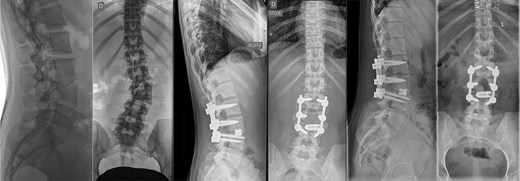

Last preoperative X-ray, lateral (A) and anteroposterior view (B). After 10 weeks of follow-up; lateral (C) and anteroposterior view (D). After 1 year of follow-up; lateral (E) and anteroposterior view (F).

Postoperatively, the patient experienced left psoas and quadriceps femoris muscle paresis, with the latter gradually improved to near-normal before discharge. No other complications were observed. At the 10-week follow-up, the left quadriceps had regained full strength, but partial paresis (3 out of 5) of the psoas muscle persisted, resulting in gait disturbance. At the final follow-up, one year after surgery, imaging showed L2-L4 fusion with no signs of instability or residual deformity (Fig. 4). The patient’s back pain resolved. A normal muscle function was observed.